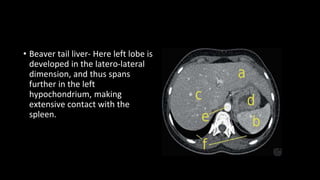

• Beaver tail liver- Here left lobe is

developed in the latero-lateral

dimension, and thus spans

further in the left

hypochondrium, making

extensive contact with the

spleen.